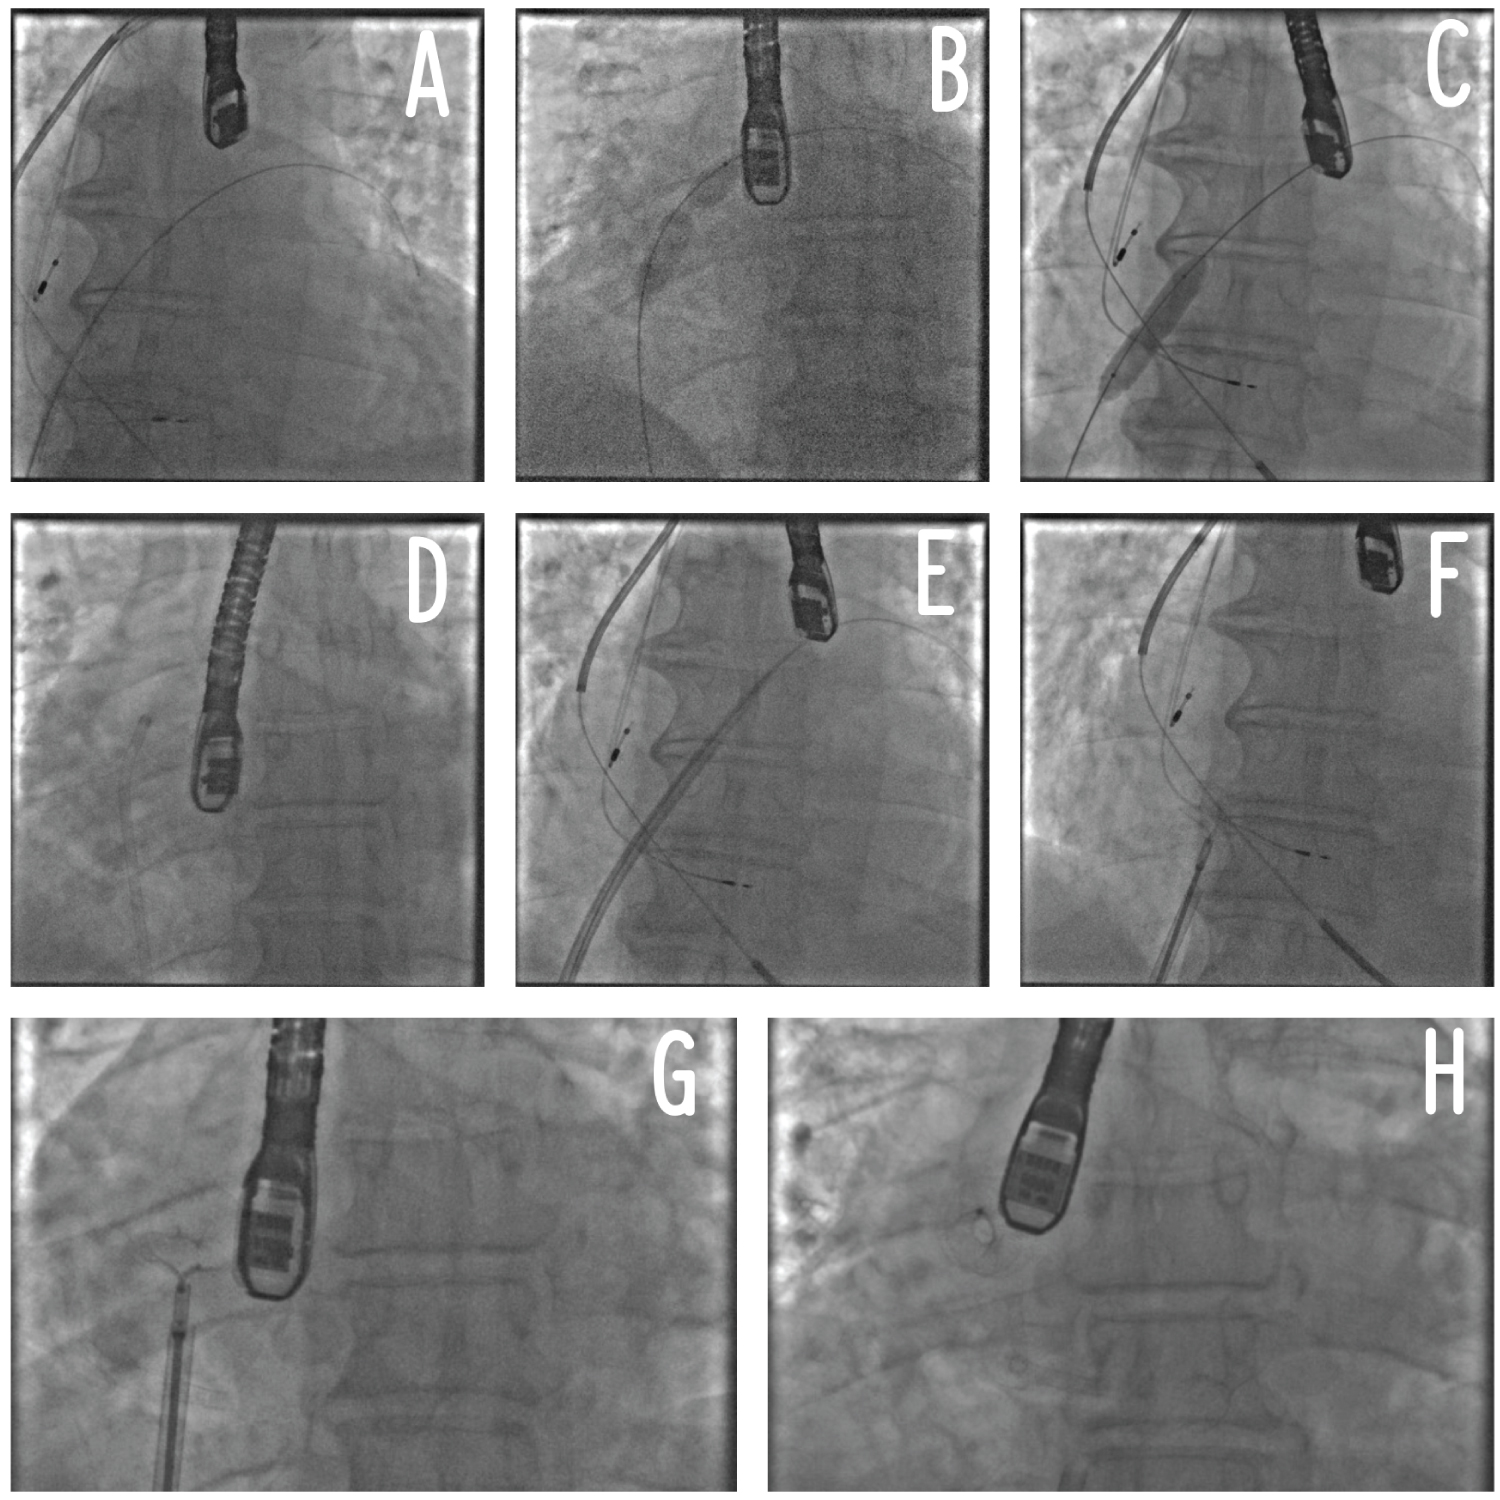

A 55-year-old man, hypertensive with type 2 insulin-dependent diabetes mellitus, dyslipidaemia and obesity (BMI: 33.96 kg/m2) underwent clinical evaluation because of more-than-3-month effort dyspnoea (NYHA III). His past medical history consisted of prior anterior ST-elevation myocardial infarction (STEMI) treated by percutaneous coronary intervention (PCI) with drug-eluting stent (DES) implantation on the left descending artery (LDA) and on the posterolateral artery (PLA). At follow-up, both DES resulted occluded while another PCI with DES implantation was performed on the obtuse marginal artery (OM1) due to a symptomatic critical CAD. A subsequent stress cardiac magnetic resonance (CMR) showed a moderate LV dysfunction (LVEF 40%) without viability of the left ventricular apex and the anterior wall. The patient was on optimal medical therapy including beta-blockers, ARNI, SGLT-2 inhibitor, diuretic, mineralocorticoid receptor antagonist). According to the recent 2021 ESC Guidelines on HF, the patient was diagnosed with advanced heart failure [1]: he presented typical symptoms of HF with persisting high N-terminal prohormone of Brain Natriuretic Peptide (NT-proBNP) and evident cardiac structural abnormalities; moreover, he had 4 episodes of pulmonary congestion requiring hospitalization, the last registered 6 months before, and developed a severe inability even to low-grade exercise. Due to this clinical scenario, the patient was admitted to our Cardiology Unit. Baseline trans-thoracic echocardiography confirmed left ventricle systolic impairment (LVEF 40%), but showed no right heart dysfunction nor severe pulmonary hypertension (e.g. pulmonary artery systolic pressure - PASP - ≥ 60 mmHg). Estimated ultrasonographic LAP at rest was 26 mmHg. Coronary angiography confirmed an occlusive in-stent restenosis on the LAD and a critical stenosis in the right coronary artery treated by DES implantation. Right heart catheterization reported mild pulmonary hypertension (PASP: 32 mmHg, diastolic pulmonary artery pressure - PAP: 24 mmHg, mean PAP: 27 mmHg) and increased PCWP at rest which was 20 mmHg. Based on these data the patient was considered a candidate for IAST using an 8-mm-diameter Atrial Flow Regulator device (Occlutech™). The procedure was successfully performed under general anaesthesia, through a hybrid fluoroscopic and transoesophageal echocardiographic guide. Procedural steps are described by Paitazoglou C, et al. [12] and are summarized in Figure 1. No complications were reported and the LAP has been acutely reduced following the generation of an iatrogenic inter-atrial shunt (final Qp/Qs 1.2) (Figure 2 and Figure 3). Patient was discharged 2 days after the procedures on dual antiplatelet therapy in association with beta-blocker, ARNI, diuretic, mineralocorticoid receptor antagonist, SGLT-2 inhibitor.

Figure 2: Fluoroscopic view of atrial flow regulator. View Figure 2